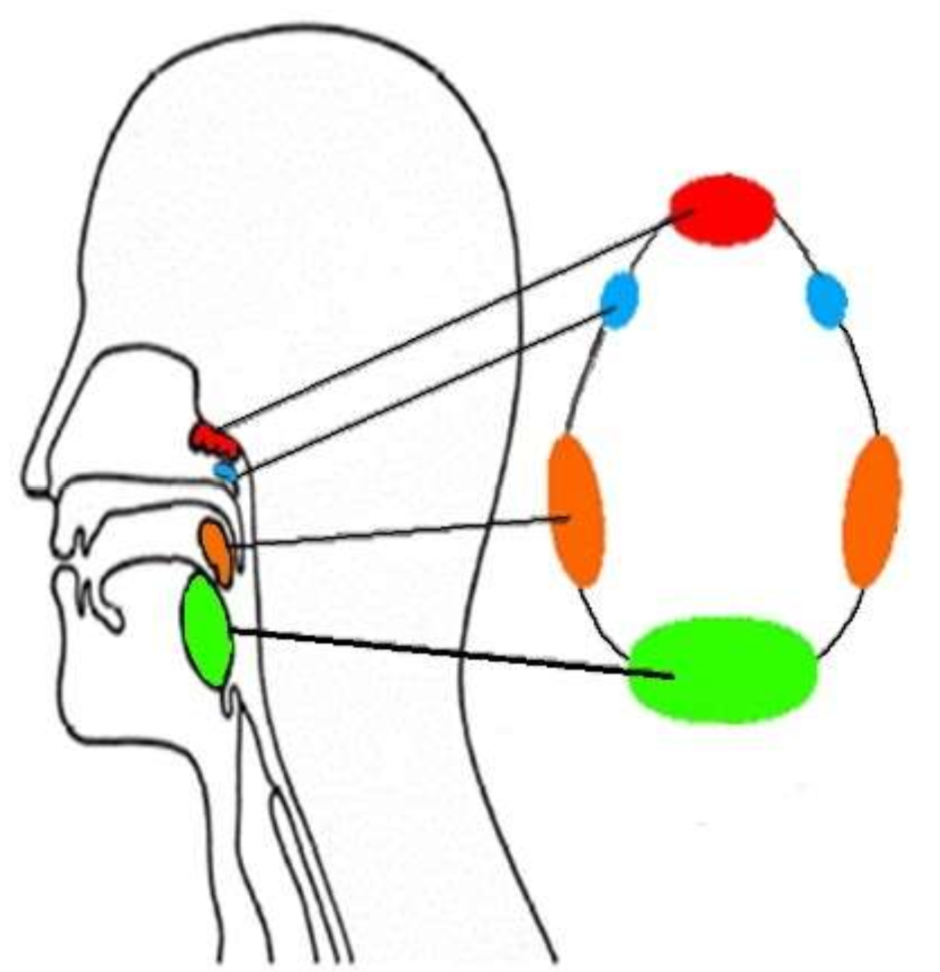

What is this group of structures called?

waldeyers ring

What is in red?

pharyngeal tonsil

What is in blue?

tubal tonsils

What is in orange?

palatine tonsils

What is in green?

lingual tonsil